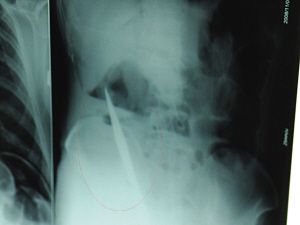

X光片上,尖刀清晰可見(jiàn)。

從男子體內(nèi)取出的尖刀足足有19厘米長(zhǎng)。

6日上午,記者在徐州礦務(wù)集團(tuán)總醫(yī)院重癥監(jiān)護(hù)室見(jiàn)到了這名男子,目前他雖然已經(jīng)恢復(fù)了意識(shí),但還不能開(kāi)口說(shuō)話,需要呼吸機(jī)輔助呼吸。據(jù)醫(yī)生介紹,4日中午12時(shí)左右,這名男子因服毒輕生被緊急送到醫(yī)院進(jìn)行搶救,之前,這名男子已經(jīng)在當(dāng)?shù)剜l(xiāng)鎮(zhèn)醫(yī)院進(jìn)行了近20小時(shí)的治療,但效果不佳。“病人被轉(zhuǎn)院到礦總院時(shí)已神志不清,血壓極低,處于休克狀態(tài)!本茸o(hù)人員給男子洗胃、初步處理以后,發(fā)現(xiàn)男子呼吸急促,于是趕緊給他拍片檢查。結(jié)果讓所有的醫(yī)生大吃一驚,竟有一把尖狀異物橫在該男子腹腔內(nèi)!當(dāng)天下午5時(shí)30分,輕生男子被推上了手術(shù)臺(tái)。經(jīng)過(guò)40多分鐘的手術(shù),該男子腹腔被打開(kāi),手術(shù)醫(yī)生發(fā)現(xiàn),男子體內(nèi)的金屬狀異物竟然是一把長(zhǎng)19厘米的尖刀!